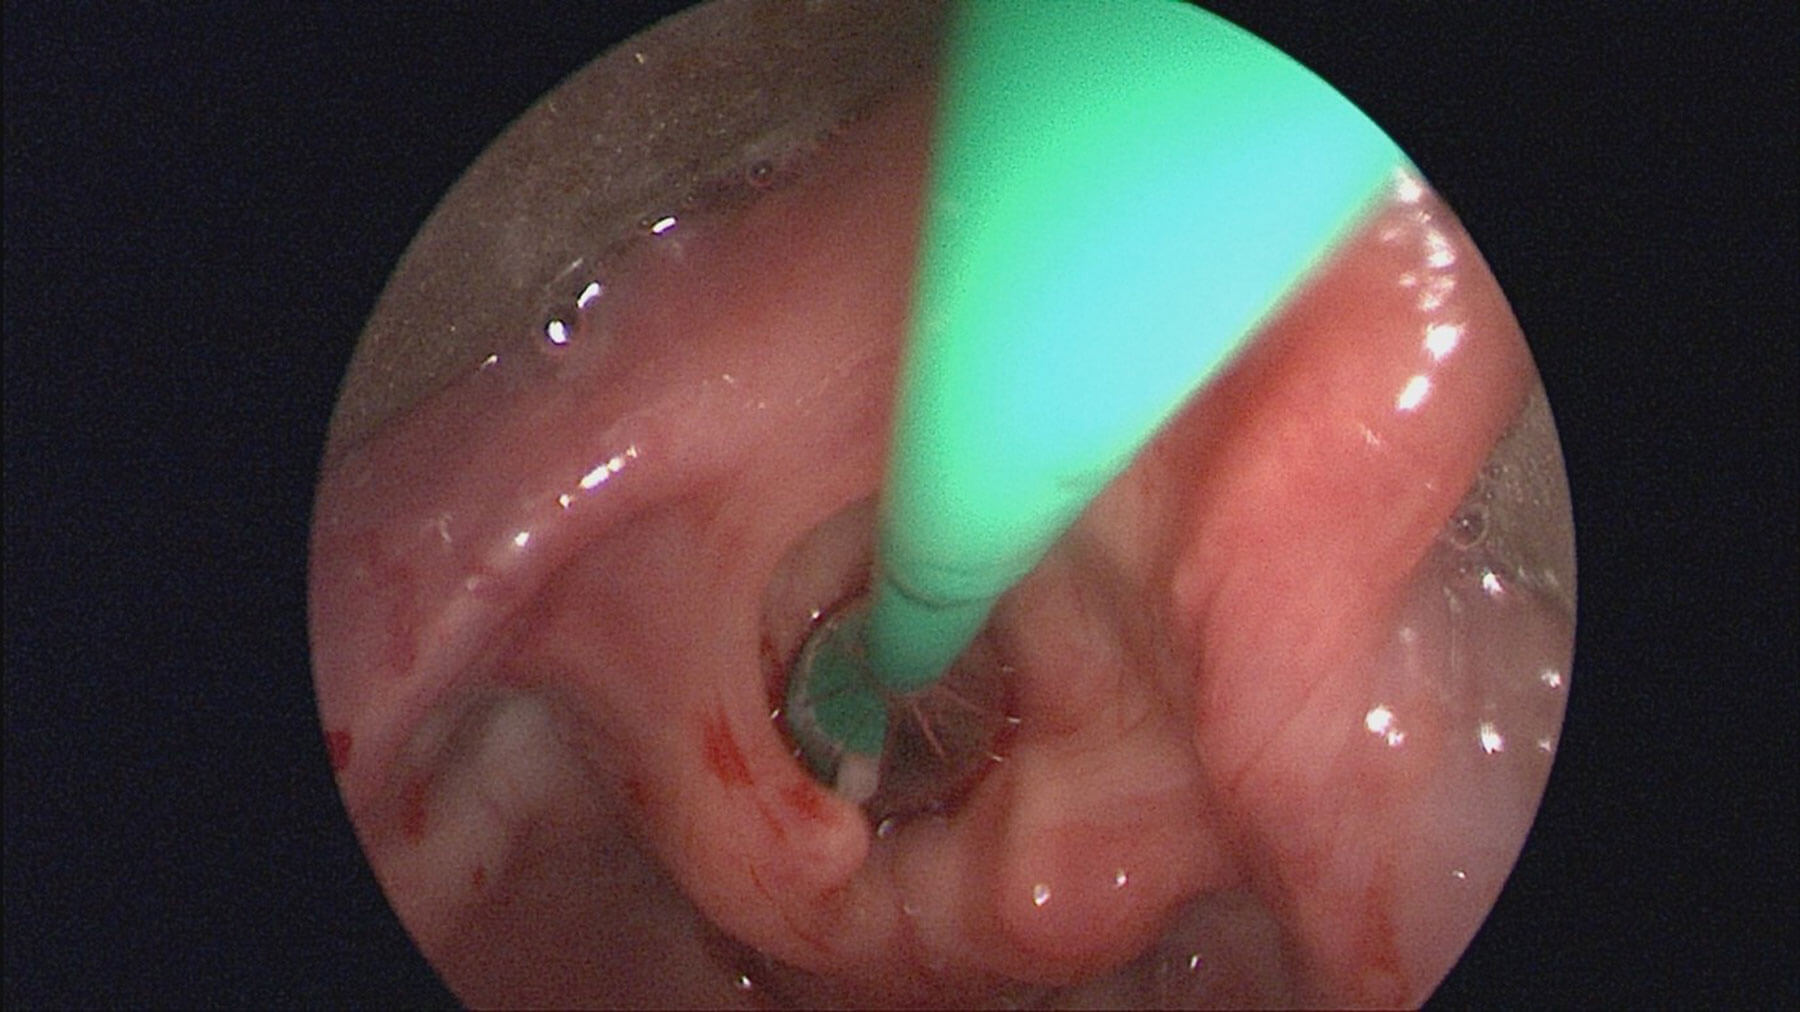

The management of airway stenosis has evolved considerably, with classic open methods now including open cricoid split and laryngotracheal reconstruction (LTR). Traditional endoscopic methods of dilatation using a bougie with dilators or endotracheal tubes have largely been replaced with endoscopic balloon dilation. Balloon dilation is largely straightforward, is associated with a short procedure time and can be particularly effective for soft immature stenosis of the airway [1] (see Figure 1). The balloon diameter is chosen based on the outer diameter of the ideal sized endotracheal tube for the patients age plus an additional 1-2mm depending on the site of stenosis [2]. Balloon dilation alone can be an effective treatment modality for subglottic stenosis, downgrading the airway stenosis enough to allow for growth of the child, or stabilising the airway prior to open definitive surgery in the form of an LTR or cricotracheal resection (CTR). Additionally, it has a very useful role in the postoperative period following open LTR to prevent early restenosis at graft sites and to keep the airway open.

Figure 1. Endoscopic view of larynx with balloon catheter in situ.